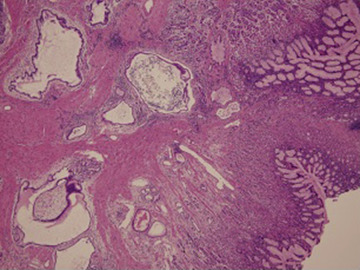

Because the studies above produced no definite diagnosis and there was a suspected malignancy, a whole layer gastric biopsy was performed under laparoscopy. Histological examination showed cystically dilated, bland-appearing, pyloric-like glandular structures in the mucosa and submucosa (Fig. 4 ). Based on these findings, GCP was diagnosed.

Laparoscopic gastric whole layer biopsy (hematoxylin and eosin, ×100). ...

Figure 4.

Laparoscopic gastric whole layer biopsy (hematoxylin and eosin, ×100). Cystically dilated, bland-appearing, pyloric-like glandular structures in the mucosa and submucosa.